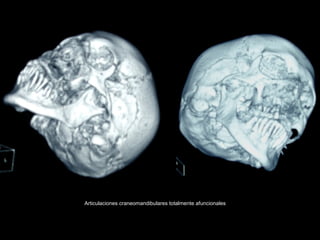

Articulaciones craneomandibulares totalmente afuncionales

Prótesis total de cóndilo, debe cuidarse la relación oclusal.

Técnica actual